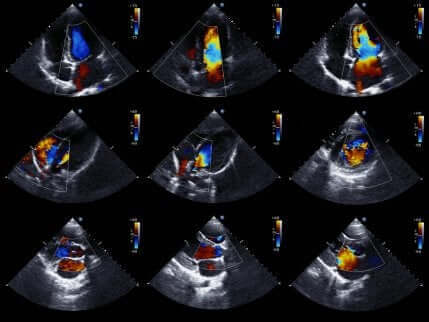

Ultraljud

Avslutningsvis låter ultraljud läkarna studera hjärtat i mer detalj.

Ultraljud är ett väldigt populärt medicinskt test eftersom det ger rörliga bilder av hjärtat. Därmed kan det utvärdera statusen hos hjärtats kammare och deras rörelse för att bekräfta eller utesluta ischemi.

Det utvärderar även hjärtats storlek och styrka, såväl som tillståndet hos väggarna i hjärtkammarna.

Det är ett icke-invasivt test som inte involverar någon risk för patienten. Detta eftersom det använder ultraljud för att få hjärtbilder.

Om läkaren använder detta test så kan frånvaron av rörelsestörningar i hjärtväggen utesluta närvaron av ischemi. Närvaron av rörelsestörningar är trots allt inte ett unikt symptom för akut kranskärlssjukdom.

Därför måste de olika testresultaten utvärderas tillsammans.